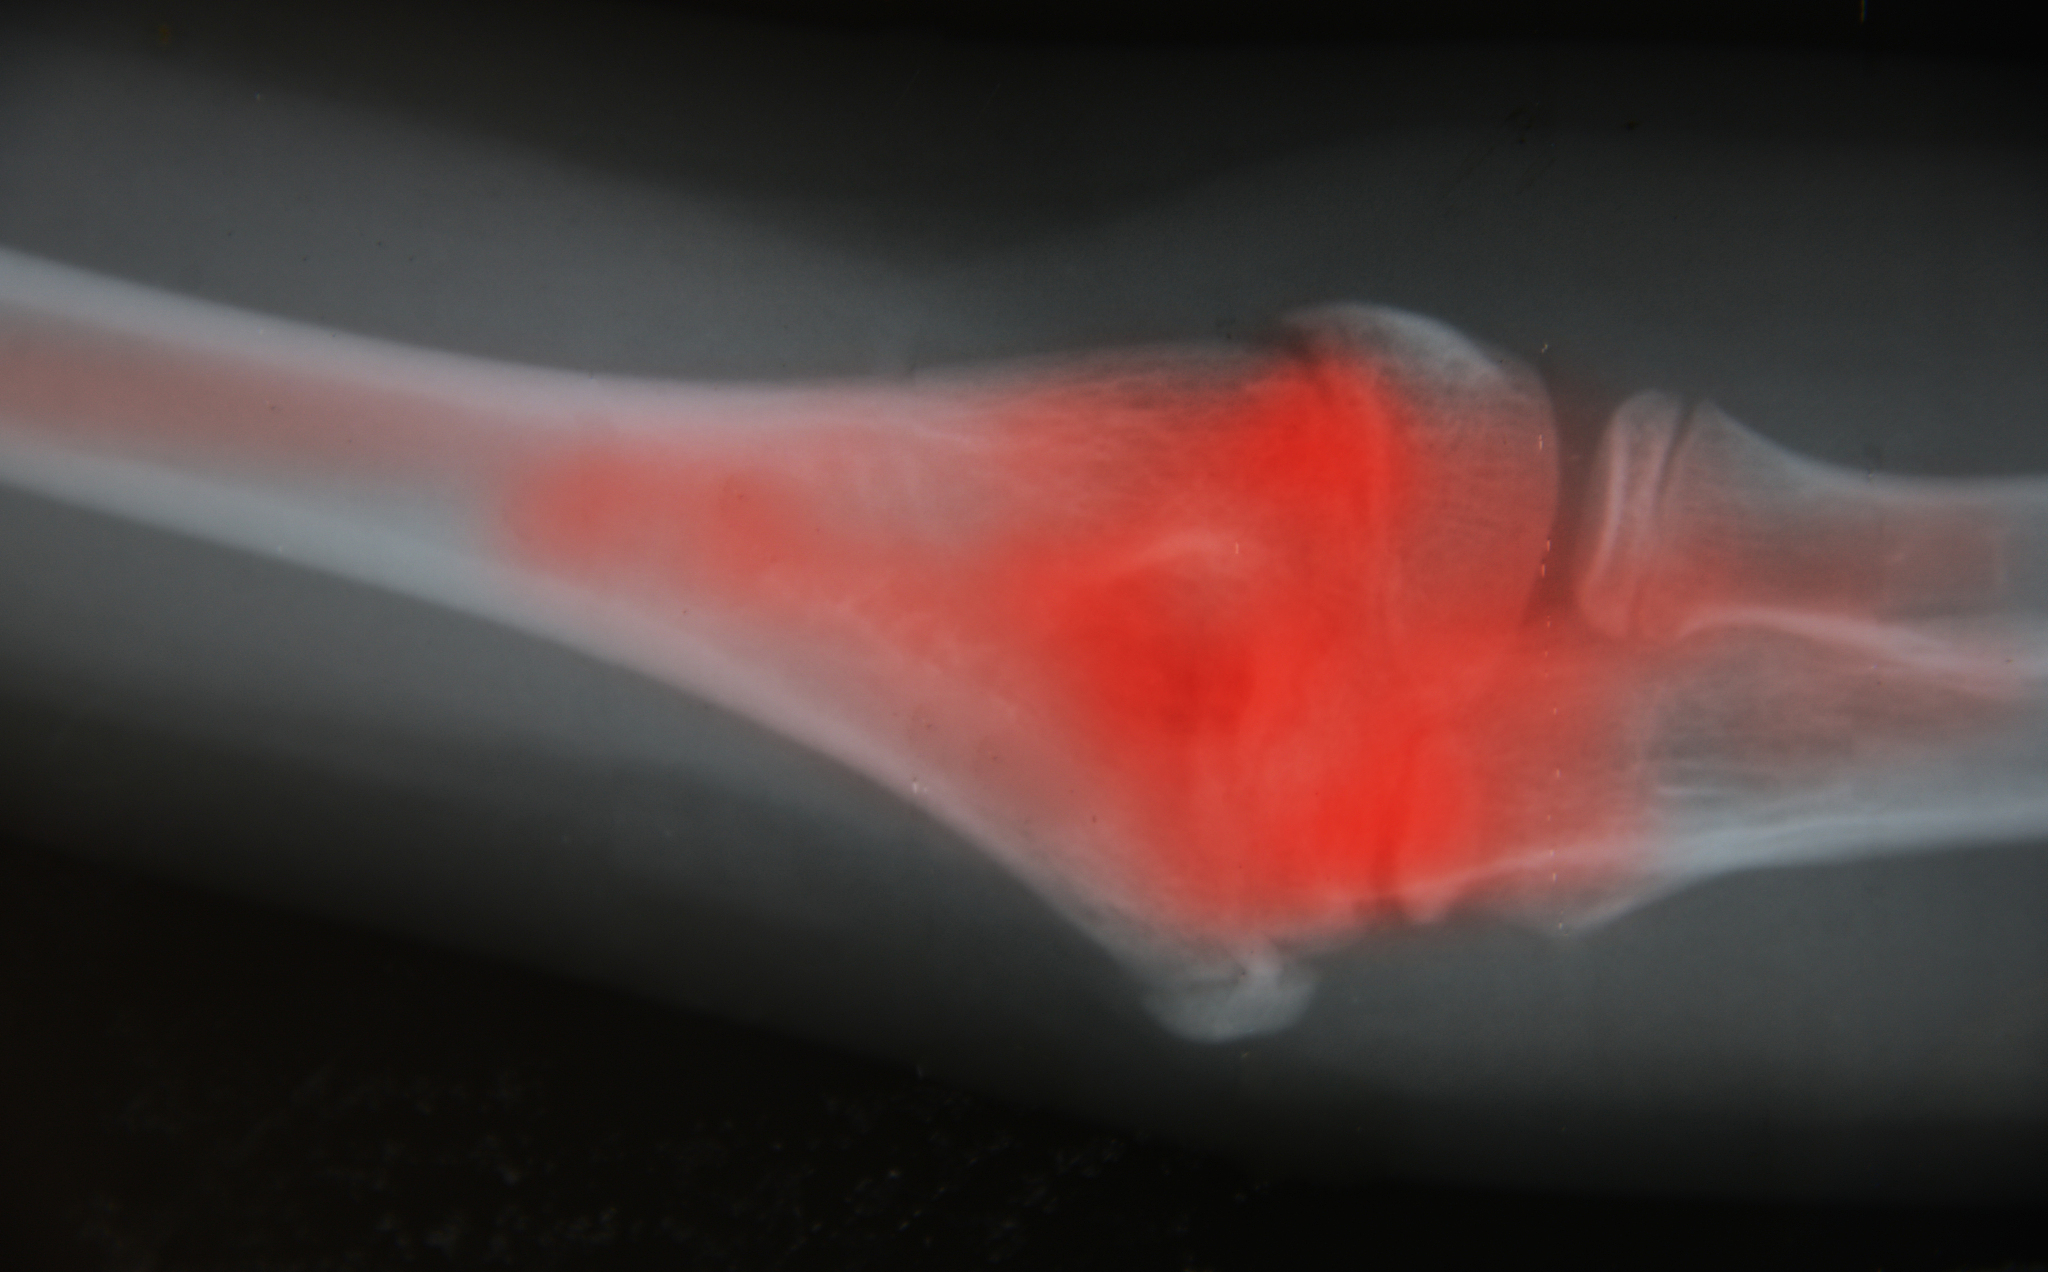

3. 骨质疏松:高龄股骨粗隆间骨折与骨质疏松密切相关,骨质疏松使骨骼脆弱易碎,增加了骨折的风险。

6. 后果严重:高龄股骨粗隆间骨折的后果严重,患者常常需要进行手术治疗,并可能导致长期的功能障碍和康复困难。